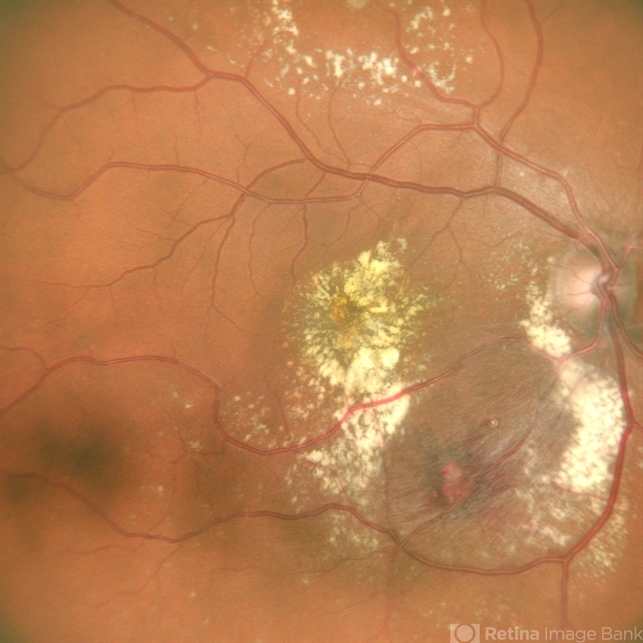

- RETINAL ARTERY MACROANEURYSM

- A 53 year old female presented with blurred vision in RE since a month ,with borderline DM and HTN not on medications .H/o highest BP recording was 160/90 mm Hg.Vision 6/60 .FFA revealed leakages. She was advised RE focal laser with intravitreal anti-VEGF injections